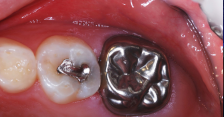

A resin-based composite had failed; the molar was sensitive, malformed, and carious.

Figure 20

Preparation for the stainless steel crown was finished.

Figure 22

The stainless steel crown, 18 months postoperatively.

Figure 23